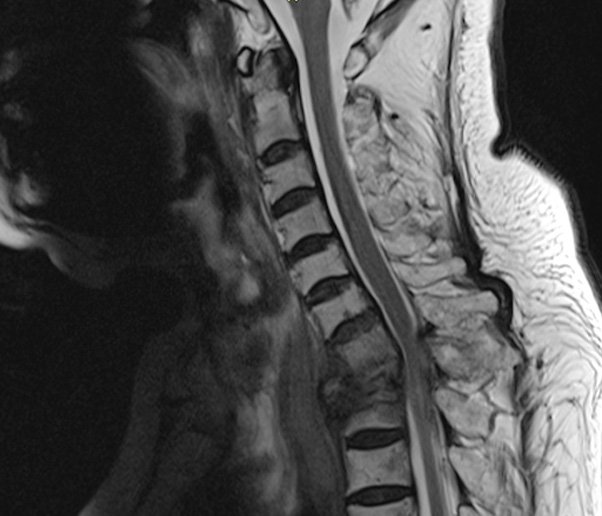

- Giai đoạn Sommer (giai đoạn 3): Trong giai đoạn này, tế bào ung thư đã lan rộng ra các bộ phận khác của cơ thể, bao gồm cả xương, gan và phổi. Đây là giai đoạn mà bệnh nhân thường bắt đầu có các triệu chứng như đau xương, mệt mỏi và suy dinh dưỡng.

- Giai đoạn Herbst (giai đoạn 4): Đây là giai đoạn cuối cùng của đa u tủy, khi tế bào ung thư đã lan rộng đến các bộ phận khác của cơ thể và gây ra các tổn thương nghiêm trọng. Bệnh nhân ở giai đoạn này thường có các triệu chứng như đau, khó thở và suy dinh dưỡng nặng.

- Đau xương: Đau xương là triệu chứng phổ biến nhất của bệnh đa u tủy. Đau có thể xuất hiện ở nhiều vị trí khác nhau trên cơ thể, nhưng thường là ở lưng, hông, và đùi.

- Sự suy giảm chức năng thận: Bệnh nhân có thể bị suy giảm chức năng thận do tế bào u tủy sản xuất các chất gây độc cho thận.